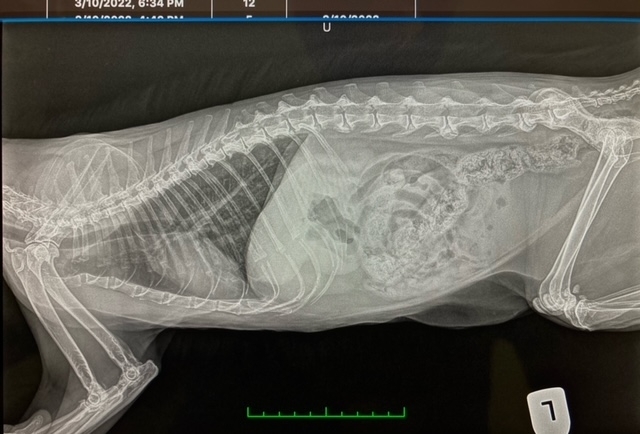

Digital x-ray equipment produces high-quality, accurate images for fast, more accurate treatment for your pet. Our clinics offer state-of-the-art digital radiology to your pets. Radiography (or X-ray) is fundamental for assessing a wide variety of ailments in pets, allows us to diagnose the severity and location of many conditions, including broken bones, tumors, bladder stones and the presence of foreign bodies (a bone, toy, or piece of clothing) in your pet's stomach or intestine. it is also useful for diagnosing heart and lung problems in your pet and can be used to evaluate hip and elbow dysplasia in dogs. Because your pet deserves the best diagnostic services, our experienced veterinarians will be evaluating and interpreting your pet's x-rays. We can also send images to a specialist for advice if necessary. We can provide you with a digital copy of your pets x-rays.